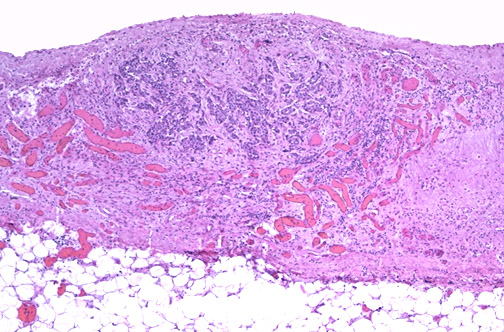

| In this small focus of metastatic carcinoma to the epicardium can be seen a key feature of neoplasms--angiogenesis. Note the proliferation of many small capillaries adjacent to the neoplastic cells. Neoplasms can produce factors that promote vascular growth to provide them a vascular supply and continued uncontrolled growth. |